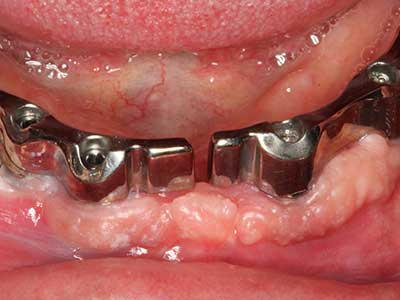

Както е показано в миналото, всяка костна хирургия представлява възможна индикация за пиезохирургия. По този начин, за препарацията на подвижни сегменти в остеогенеза (Фиг. 23-25) и остеотомия се използват специални накрайници, без да се застрашава снабдяването с кръв в кресталната зона, което е от съществено значение за успеха и на двете техники (Gonzalez-Garcia, Diniz-Freitas et al. 2008).

За отстраняването на имплант, вестибуларното костно покритие, което е заменено след премахване на импланта, може да бъде оформено, за да задържи контура на алвеоларния гребен.